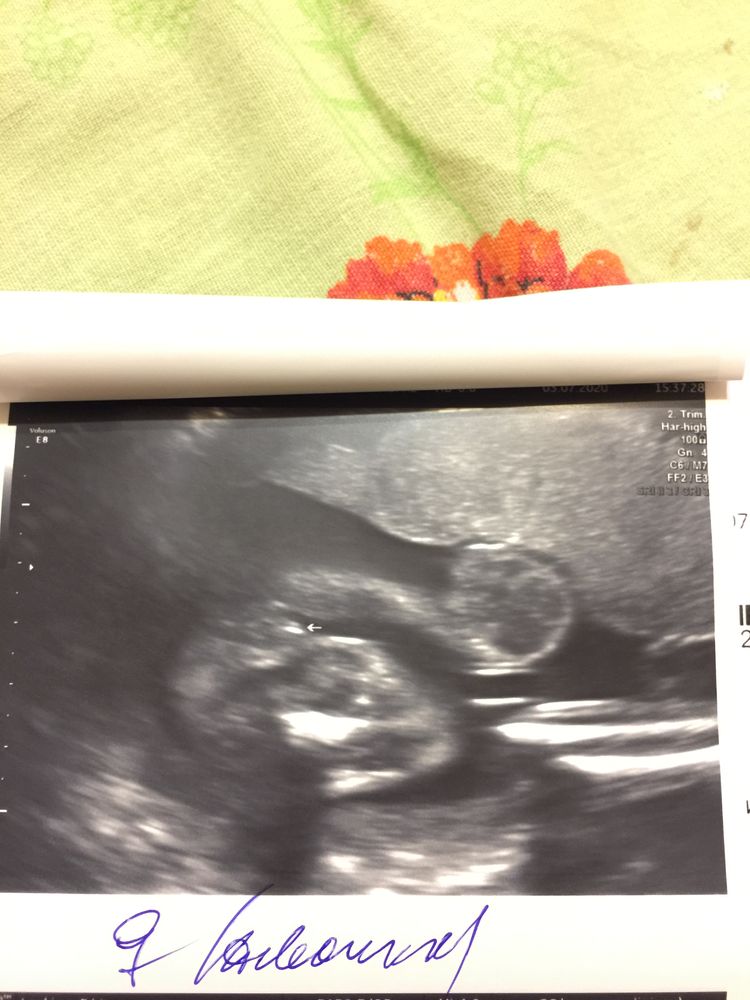

Только такое в наличии, около этих сроков.

От 20+ недель уже прям отчетливо было видно.